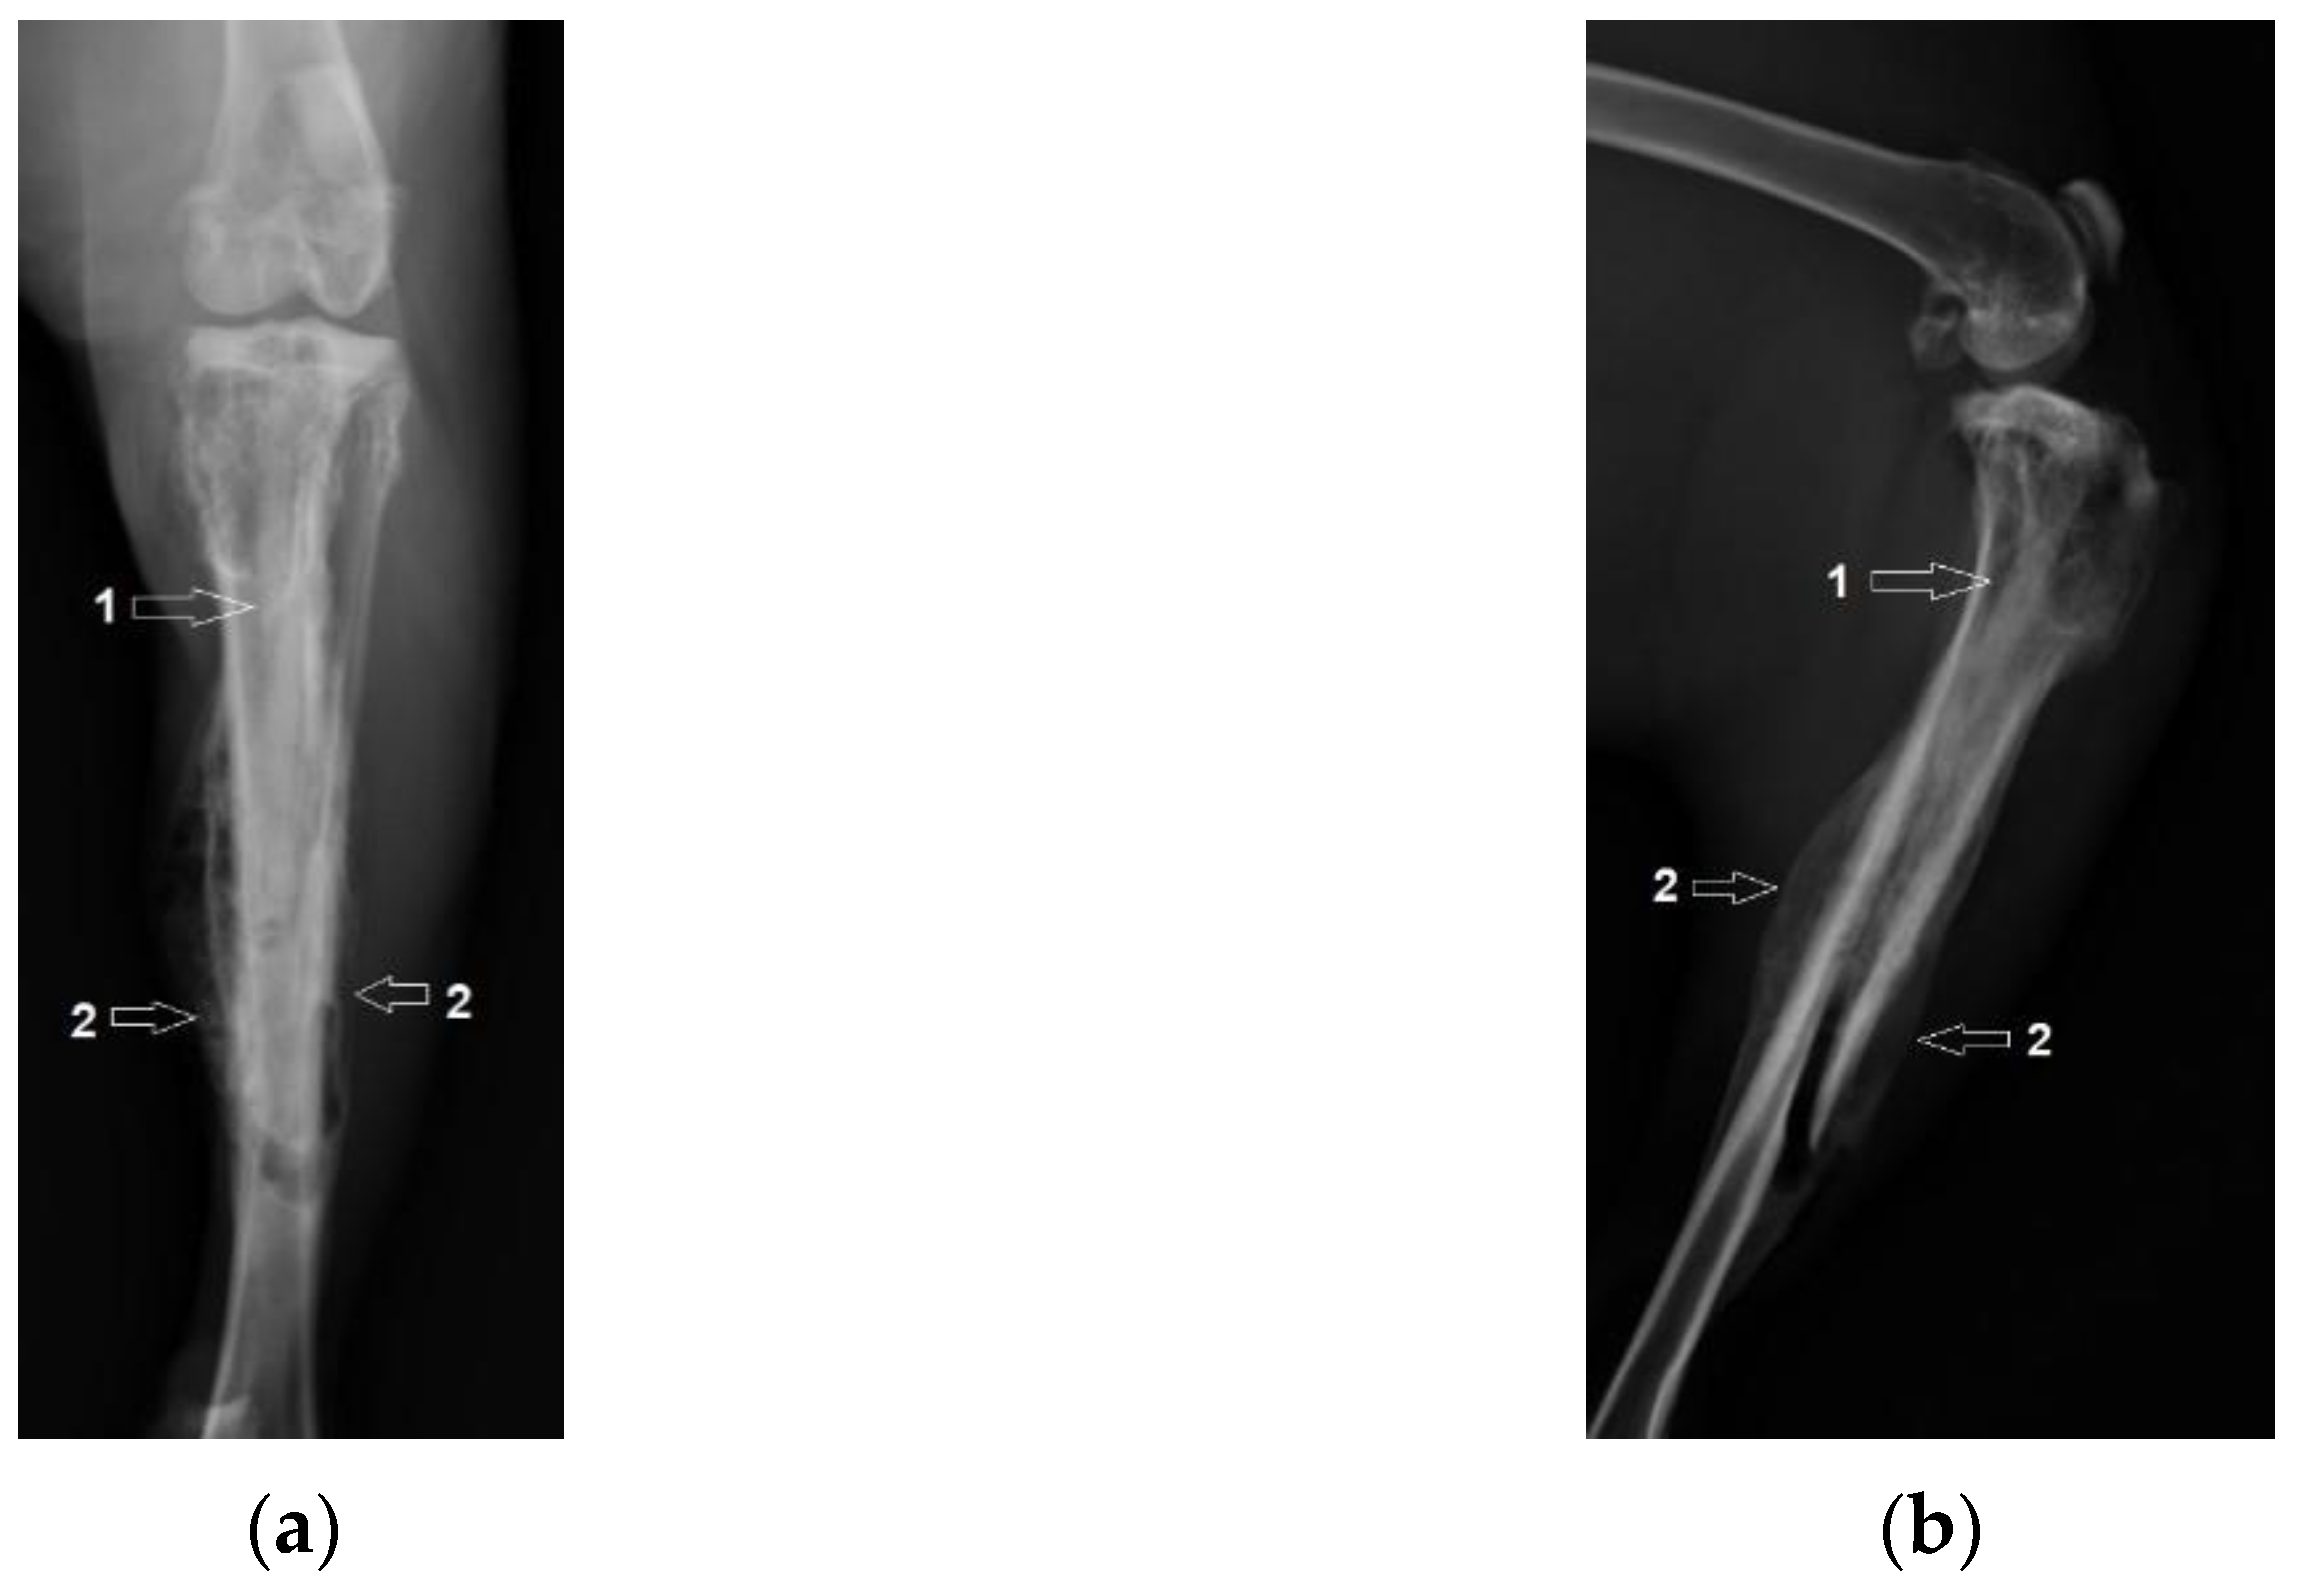

3.1. Radiological Followup